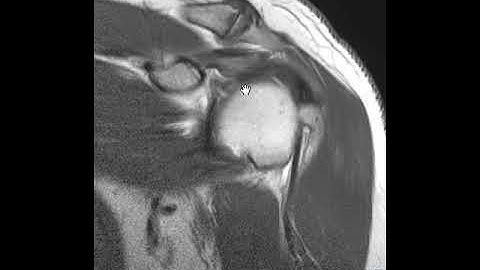

Shoulder Compression Rotation Test for Labral Tears | Technique Peek Series